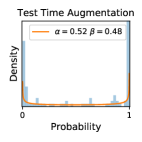

5.1 Distribution of Uncertainty Scores

Distribution of Uncertainty Scores Across Different Severity Levels As explained in Section 3, each uncertainty metric essentially defines an order/ranking among the data points. We conducted an analysis to better understand what data will be assigned high uncertainty under a particular uncertainty metric . Picking out the highest ranked data points (), we calculated the ratio of data points from each SL. Figure 4 summarizes the results as box plots for the Kaggle-DR and the Messidor-2 datasets; additional detailed statistics can be found in Table S.1 in the supplementary materials. From the plot and table, SL1 & SL2 examples account for a higher proportion among the top-ranked uncertain examples across the three ensemble methods. This finding matches our intuition that incipient disease examples (SL1 & SL2) are more likely to be considered uncertain by ensemble methods due to their ambiguity.

Comparing the three ensemble methods in Figure 4, the stacking ensemble method has the highest ratios of SL1 & SL2 data among the high-uncertainty examples it identified under both mean and var. TTA showed slightly better performance than MC-dropout but still falls behind the stacking ensemble method. Considering the fact that SL0 examples accounted for the majority of the dataset, the stacking ensemble method was much more precise (specific) in selecting truly ambiguous data points that were difficult to classify. From Figure 3, we can also see that the stacking ensemble method greatly outperformed the other two methods in finding false negatives under both mean and var uncertainty metrics.

In contrast, the MC-dropout method showed the worst overall performance among the three, as it can be seen from the high ratios of SL0 examples among the uncertain negatives in Figure 4. The histograms in Figure 2 provides another perspective to look into the phenomenon, where a decent proportion of MC-dropout model’s predictions on SL0 inputs entailed low confidence (far from 0 or 1), which from another angle explained why MC-dropout was less specific in terms of lower FNP; many no-DR inputs (i.e. SL0) were erroneously assigned high uncertainty by MC-dropout models.

It is still an open question why the evaluated MC-dropout networks signaled relatively high uncertainty on SL0 & SL3 & SL4 data that are less likely to be ambiguous. We conjecture that much of the “uncertainty” indicated by disagreement among test-time dropout samples actually reflects the stochastic nature of dropout networks rather than the real decision uncertainty associated with the data. It is worth noting that the MC-dropout model we evaluated was not weak per se; they all achieved above Area Under Curve (AUC) scores on test sets. The weakness of individual test-time samples (which explains their low-confidence predictions on SL0 & SL3 & SL4) might have been hidden when they are aggregated into an ensemble—a well-known advantage of ensemble learning. Our results suggested that the uncertainty information given by implicit ensemble methods such as MC-dropout and TTA might not be as reliable as that from explicit ensemble approaches (e.g., stacking ensembles). Similar findings on MC-dropout can be found in some previous papers [1].